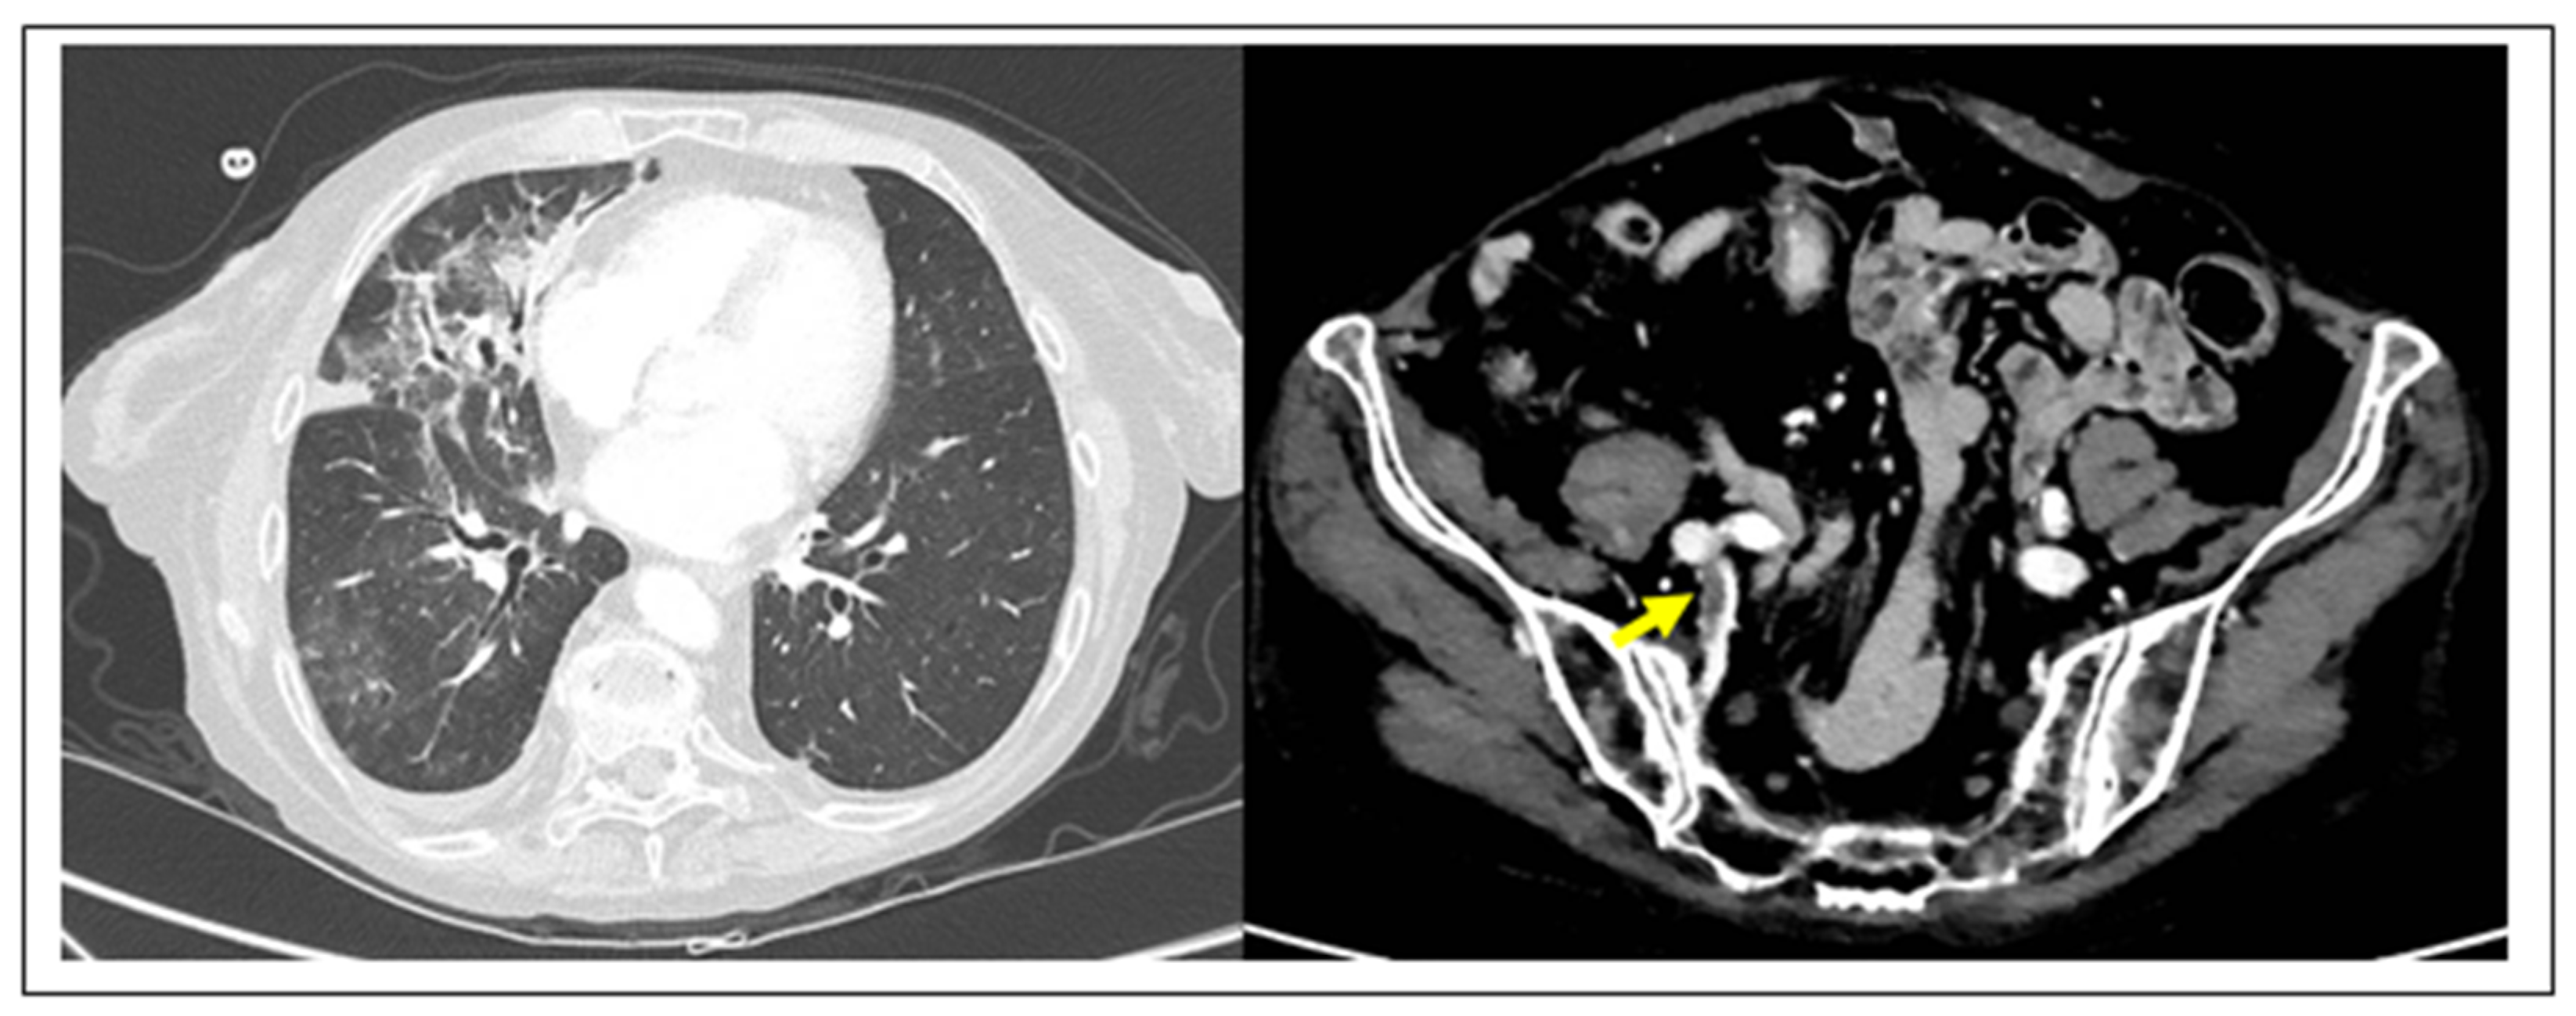

In the past few months, blood clots have emerged as the common factor unifying many of the mysterious symptoms attributed to COVID-19, a disease that had initially been thought to largely affect the lungs in the form of pneumonia. Early findings in COVID-19 autopsies showed deep vein thrombosis (DVT) in 58% of cases, complicated by fatal venous thromboembolism (VTE) in 30% of patients. In addition, sudden cardiac death and kidney infarct complications were found in the other 30% of patients of this initial cohort [18]. Recently, the hypothesis that COVID-19 pneumonia might be complicated by VTE has been supported by an increased number of reports in the COVID-19 literature [19,20,21,22,23,24] (Figure 1).

Figure 1.

TC imaging of DVT complication in COVID-19 pneumonia. (Left) COVID-19 pneumonia with typical association of ground glass opacities and thickening of interlobular septa, particularly visible at the level of the right lung. (Right) The same case complicated by right hypogastric DVT (yellow arrow) (D-dimer 5.52 2.0 µg/mL).